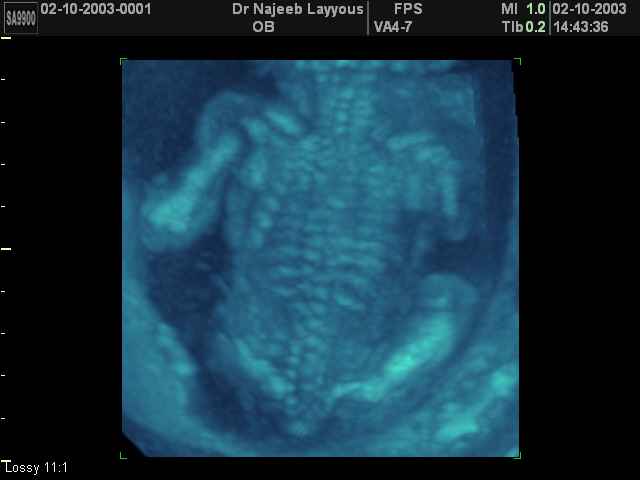

- Fetal Skeleton Ultrasound Photos